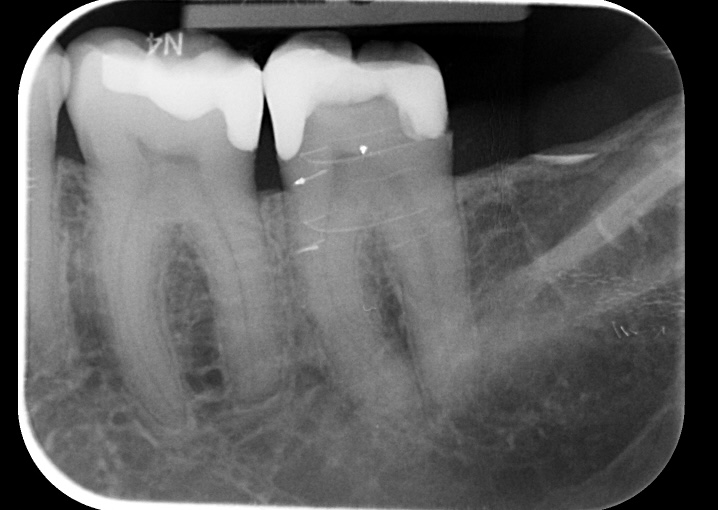

Maar ze zei ook dat er nog een breuk zat binnen in (volgens mij op de foto rechts.

De betreffende RX foto